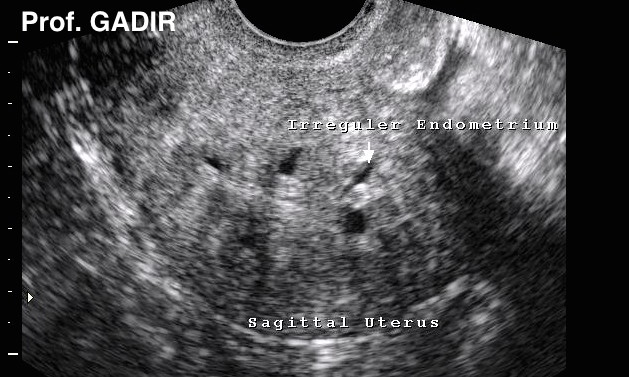

Diagnosis

The uterus is usually enlarged but regular in shape. It could be tender during bimanual vaginal examination.

Previously histological examination of hysterectomy specimens was the only means for diagnosing adenomyosis. However recently both MRI and transvaginal scan examinations are used for the pre-surgical diagnosis of the disease.

MRI is very sensitive in showing widening of the junctional zone but transvaginal scan examination is also 80% sensitive in diagnosing adenomyosis. Moreover transvaginal scanning facilitates needle biopsy and histological examination of suspected areas.